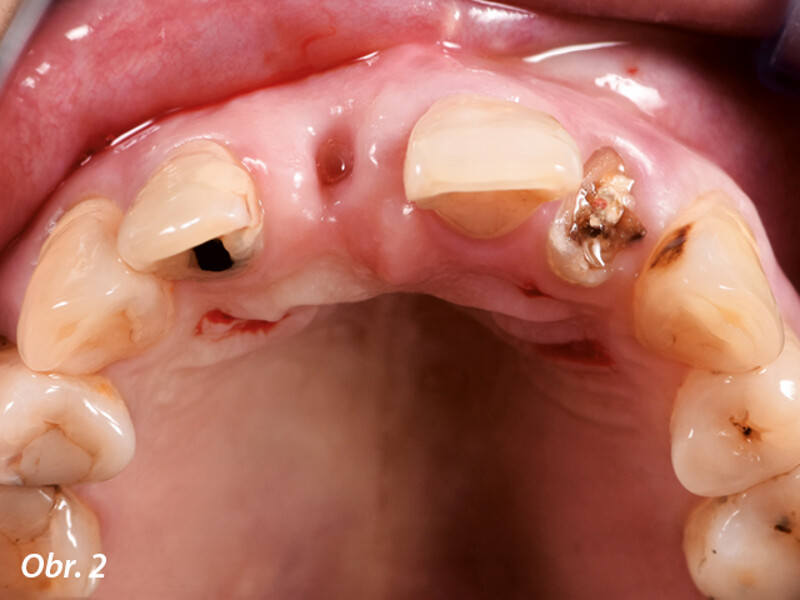

Okamžitá implantace a CADCAM